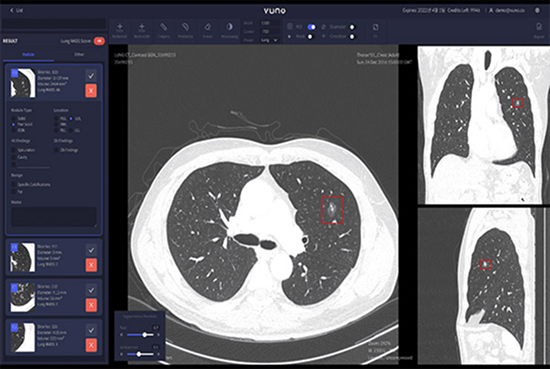

VUNO Med-LungCT’s competitive edge is about its performance. An AI-based product that assists lung diseases diagnosis, it also provides data on nodules’ size, volume, and location.

Results are integrated with PACS in the format of GSPS objects, which ensures great user convenience.

Lung Nodule Detection & Measurement

•  High Sensitivity, 93% Sensitivity per 1 FP, based on performance validation with open dataset LUNA16

•  Optimized nodule detection performance through super-resolution algorithm

•  Detects nodules between 4mm — 30mm

•  Provides volumetric data of nodules

•  Provides a mask feature to detect part-solid nodules (Overall, Ground-glass, Solid Part)